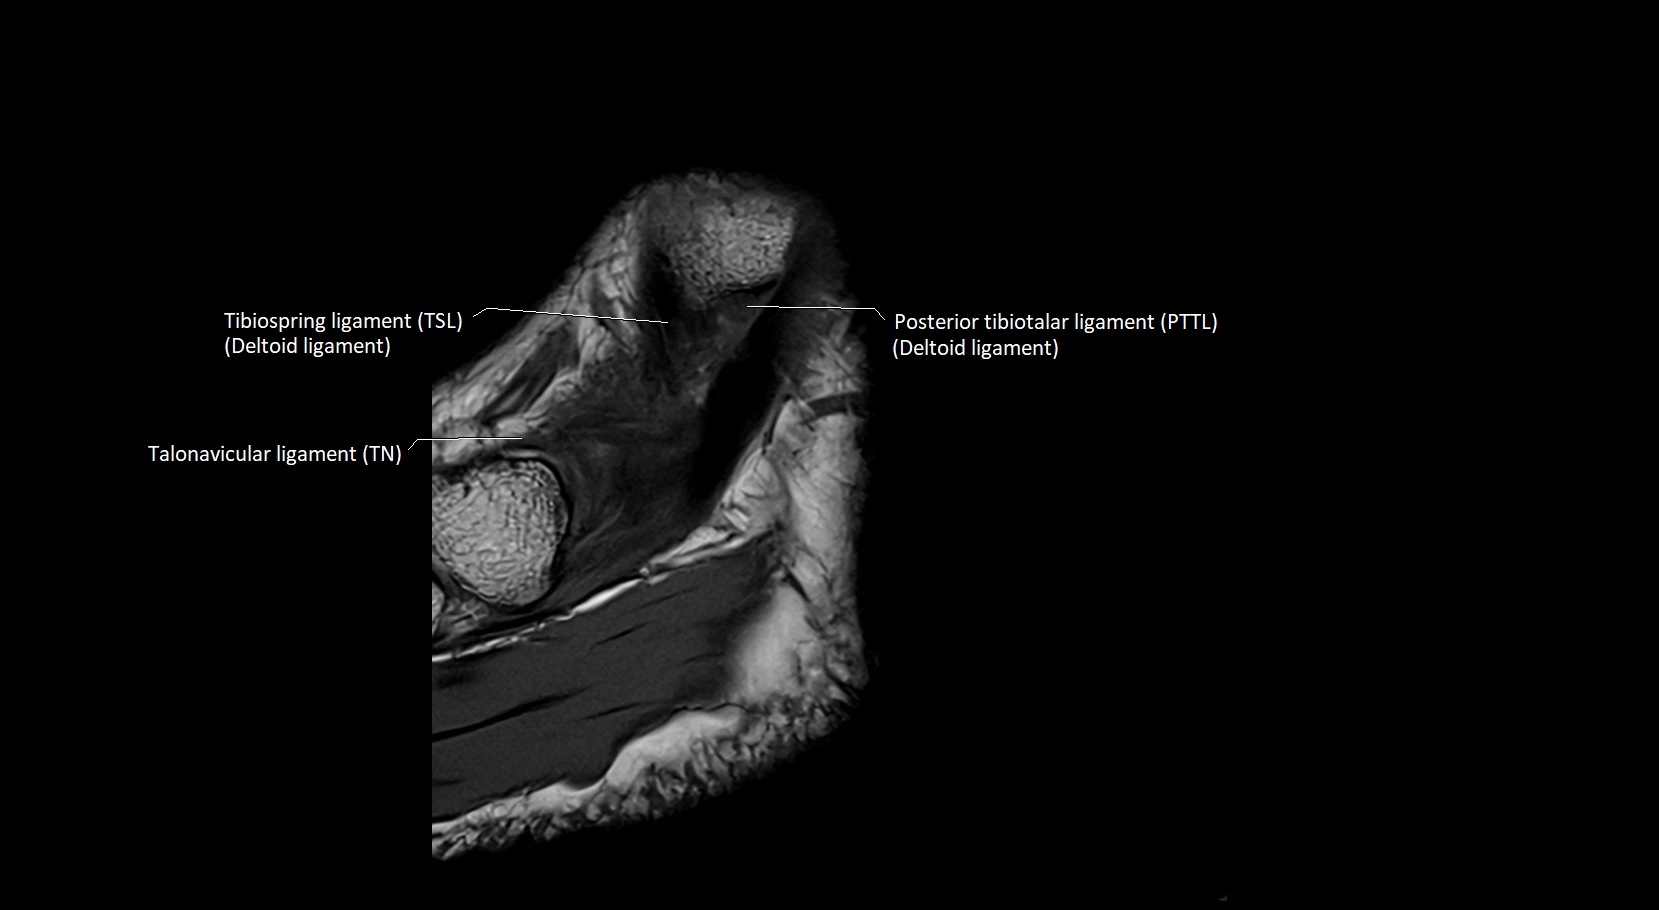

MRI image

image